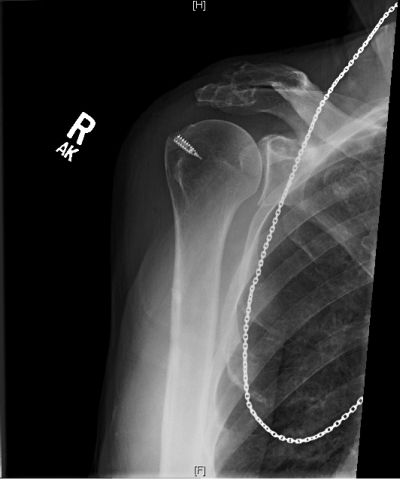

Before After

Before After (Screw Shows Up)

Surgery Pattern A Tad Bit Of Brusing.